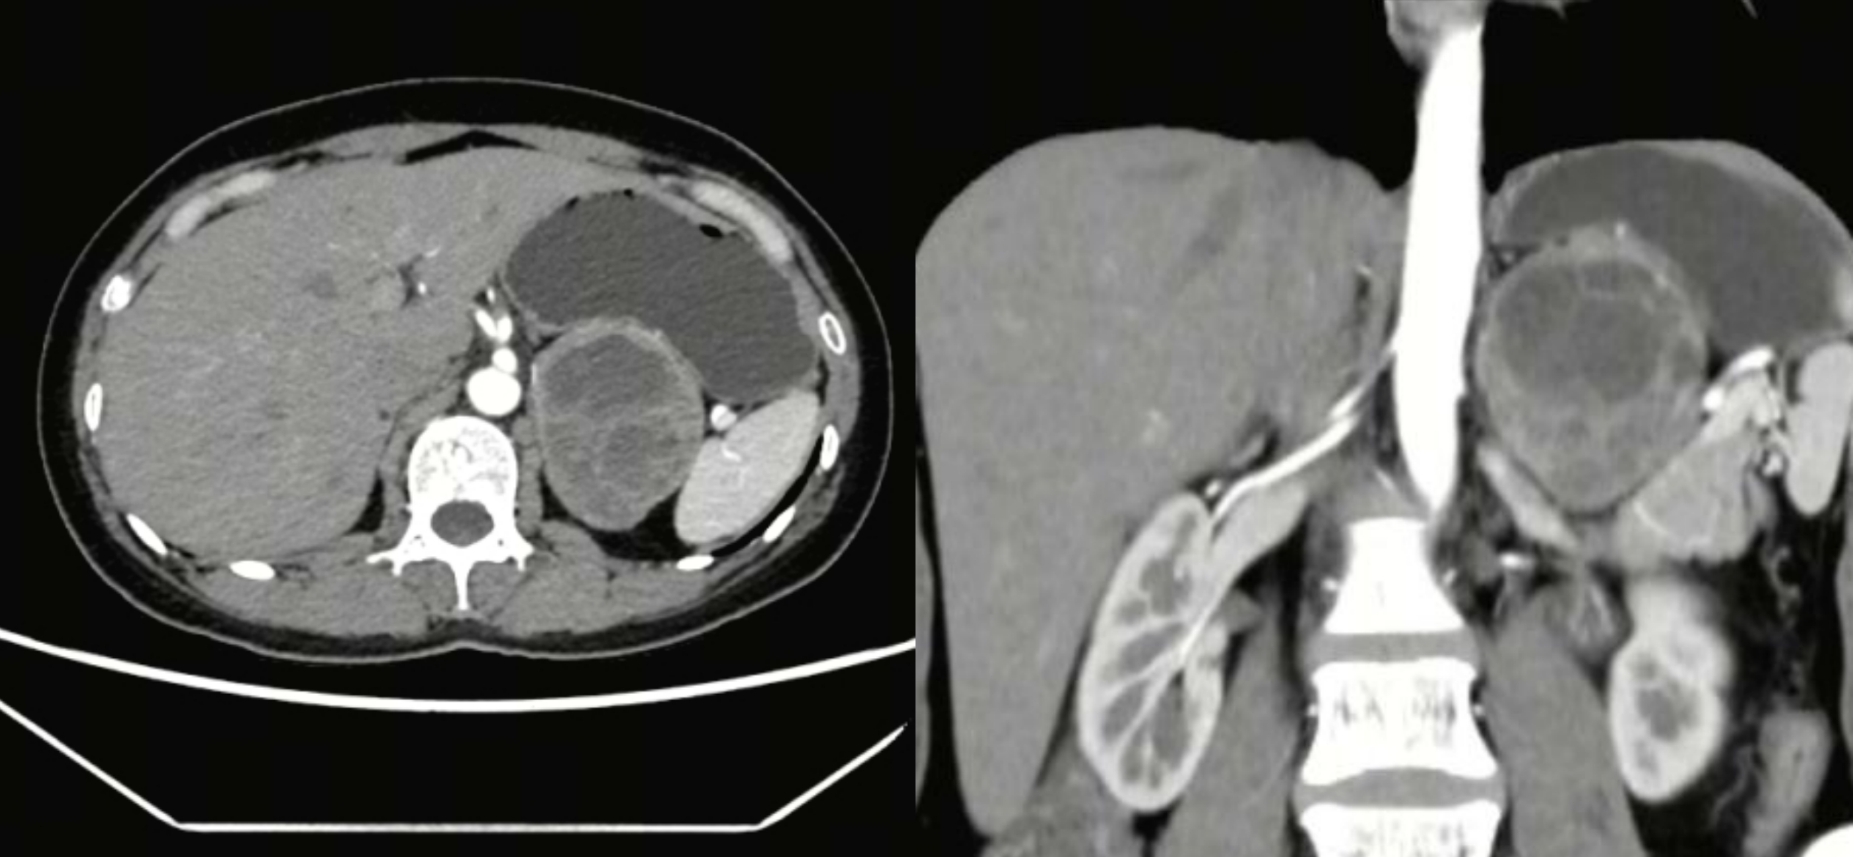

患者余女士,因“体位改变后反复出现心悸、心慌不适3年”于门诊就诊,入院后完善相关检查,考虑为嗜铬细胞瘤,检查发现左侧肾上腺肿瘤大小约68mm×56mm×63mm,手术指征明确。嗜铬细胞瘤术中存在血压剧烈波动可能,为降低术中血压波动,术前给予应用 α 受体阻滞剂2周及扩容治疗,减少最高收缩压或高血压诱发的心脑血管意外的影响。我院泌尿外科肖运政主任克服重重困难,联合“三名工程”团队与我院影像科、麻醉科、内分泌科、心血管内科专家启动多学科诊疗(MDT),制定了“拆弹”方案——腹腔镜左侧嗜铬细胞瘤切除术。